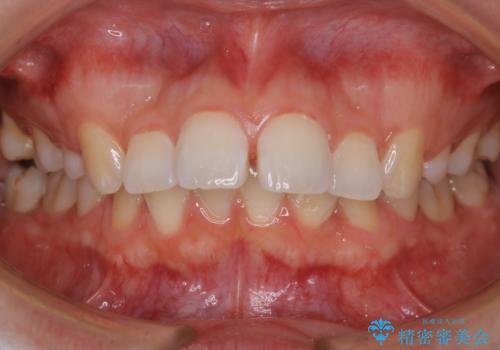

前歯で咬めない・出っ歯 抜歯矯正で整った上下の前歯へ